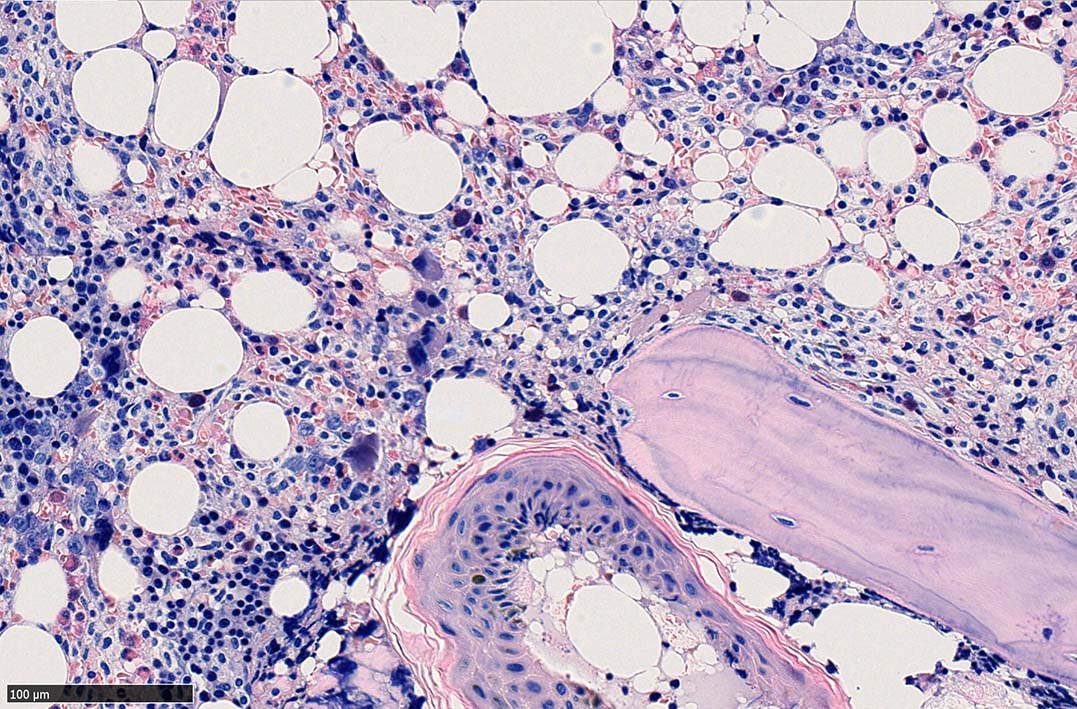

bone marrow trephine biopsy: dry tapのため骨髄生検が行われる. cellularityは40-80%とhypercellular marrow. 流れのある細胞配列は線維化を疑わせる.

ASD-G 低倍率所見では赤芽球血島は幼若赤芽球の集簇巣が散在する, 顆粒球系細胞(ASDに赤く染色される)は減少,granulopoietic hypoplasiaを呈する.疎な集簇を示すmast cellsの増加がある.

ASD-G陰性の細胞がびまん性に増加しているように見える.

ASD-Giemsa陰性の細胞がシート状に増殖する. 核はクロマチン濃染, 核小体は不明瞭.類円形, 卵円形, くびれを持つ多稜形核, 長円形いびつで屈曲した核, など多彩. 細胞質は淡清色調, 広く淡明. 赤芽球血島は幼若赤芽球のみで形成される異形成像を示す. やや離れて成熟赤芽球が疎な集簇を示す.

Ag染色では, 疎な弾性線維が増生し,増殖細胞を小胞巣状に分画するいわゆる「lymphomatoid pattern」を呈する. 本例では, Mgkに異形成所見がある.